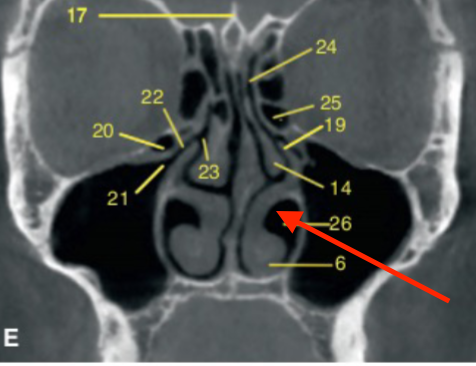

coronal

what plane is this slice

middle turbinates/concha

identify the structure

inferior nasal meatus

identify structure

nasal septum

nasolacrimal duct

ostium (of maxillary sinus)

uncinate process

sphenoid sinus

frontal sinus

ethmoid air cells

identify the structures

orbit

infraorbital foramen

what plane

posterior of maxillary sinus

where is this slice

mental foramen (at premolar region)

molar region

where is this slice located

mandibular canal/inferior alveolar canal

what is the ARROW pointing to

orbital roof

what are the arrows pointing to

nasal floor

identify the structure indicated by the ARROW

midline (presence of septum)

what is the location of this slice

nasal bone

inferior turbinate/cochae